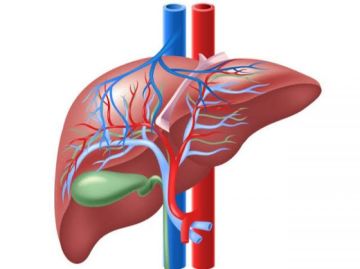

قالت منظمة الصحة العالمية في بيان لها، إنه مع احتفالنا باليوم العالمي لالتهاب الكبد، تدعو منظمة الصحة العالمية الحكومات والشركاء إلى تسريع الجهود بشكل عاجل للقضاء على التهاب الكبد الفيروسي باعتباره تهديداً للصحة العامة والحد من الوفيات الناجمة عن سرطان الكبد.

يُعد التهاب الكبد الفيروسي - الأنواع A وB وC وD و E من الأسباب الرئيسية لالتهاب الكبد الحاد، ومن بين هذه الأنواع، وحدها أنواع التهاب الكبد B وC وD يمكن أن تؤدي إلى التهابات مزمنة تزيد بشكل كبير من خطر الإصابة بتليف الكبد أو فشل الكبد أو سرطان الكبد.

ومع ذلك، لا يعلم معظم المصابين بالتهاب الكبد بإصابتهم، تُصيب الأنواع B وC وD أكثر من 300 مليون شخص حول العالم، وتُسبب أكثر من 1.3 مليون حالة وفاة سنويًا، معظمها بسبب تليف الكبد والسرطان.

تم تصنيف التهاب الكبد الوبائي' د ' الآن على أنه مرض مسرطن، صنّفت الوكالة الدولية لبحوث السرطان (IARC) مؤخرًا التهاب الكبد الوبائي' د '، على أنه مُسرطن للبشر، تمامًا مثل التهاب الكبد الوبائي B وC يرتبط التهاب الكبد الوبائي' د'، الذي يُصيب المصابين به فقط بخطر الإصابة بسرطان الكبد أعلى بمرتين إلى 6 أضعاف مقارنةً بالتهاب الكبد الوبائي B وحده، ويمثل هذا التصنيف الجديد خطوةً حاسمةً في الجهود العالمية الرامية إلى رفع مستوى الوعي، وتحسين الفحص، وتوسيع نطاق الوصول إلى علاجات جديدة لالتهاب الكبد الوبائي' د'.